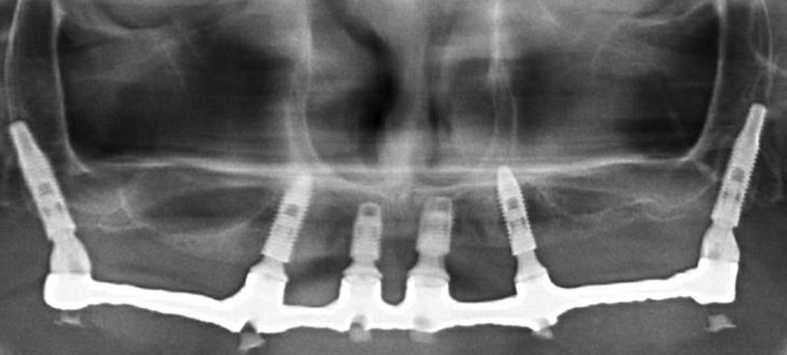

Instalação Implantes

Radiografia Pós-cirurgica

- Overdentures e Protocolo de Branemark

- Planejamento reverso e Guias Cirúrgicos

- Implantes de formatos especiais – Curtos | Angulados | Estágio único

- Carga Imediata e Implantes Imediatos

- Pilares esqueléticos – Implantes Zigomáticos e Implantes

- Pterigóideos